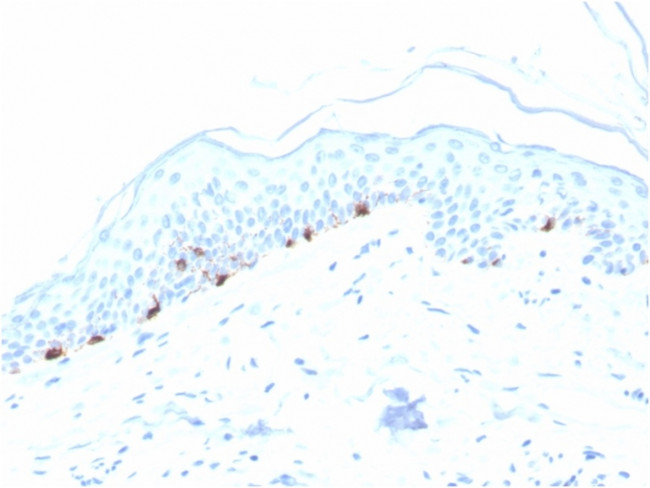

Tyrosinase-Related Protein-1 (TYRP-1) (Melanoma Marker) Antibody in Immunohistochemistry (Paraffin) (IHC (P))

Tyrosinase-Related Protein-1 (TYRP-1) (Melanoma Marker) Antibody (7306-MSM10-P1ABX) in IHC (P)

Formalin-fixed, paraffin-embedded human Skin stained with TYRP1-Monospecific Mouse Monoclonal Antibody (TYRP1/3280). {{ $ctrl.currentElement.advancedVerification.fullName }} 验证信息 View more